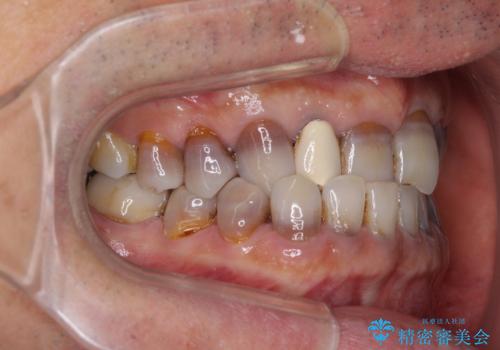

インビザラインは四六時中上下のマウスピースを介した咬合状態となるため、治療過程にて奥歯が接触しないという状態が続くことがあります。

奥歯の非接触は機能面において大きな障害であるため、この問題を解決しない限り矯正治療を終えることはできません。

インビザラインでの矯正治療が長期化してしまう要因の1つです。